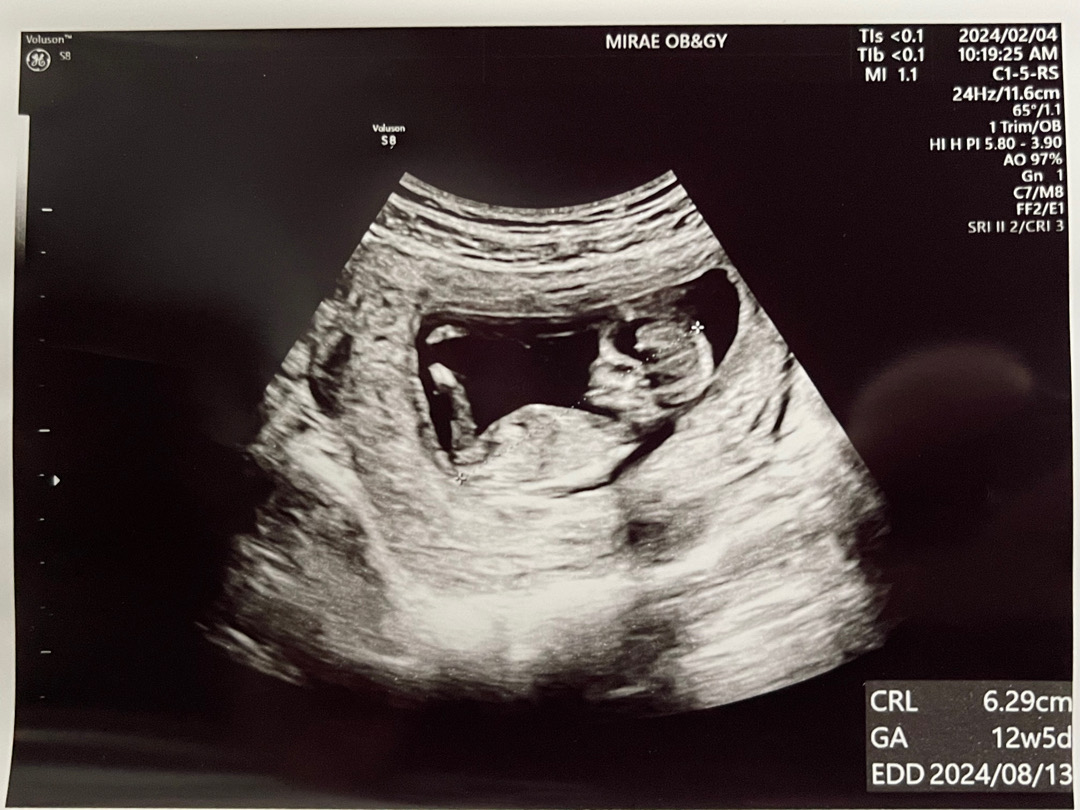

12주 3일 이것은 남자인가 여자인가

저는 여자애인것 같다고 하고 남편은 남자애인것 같디고 하네요..다른 분들은 어떻게 보이시나요?